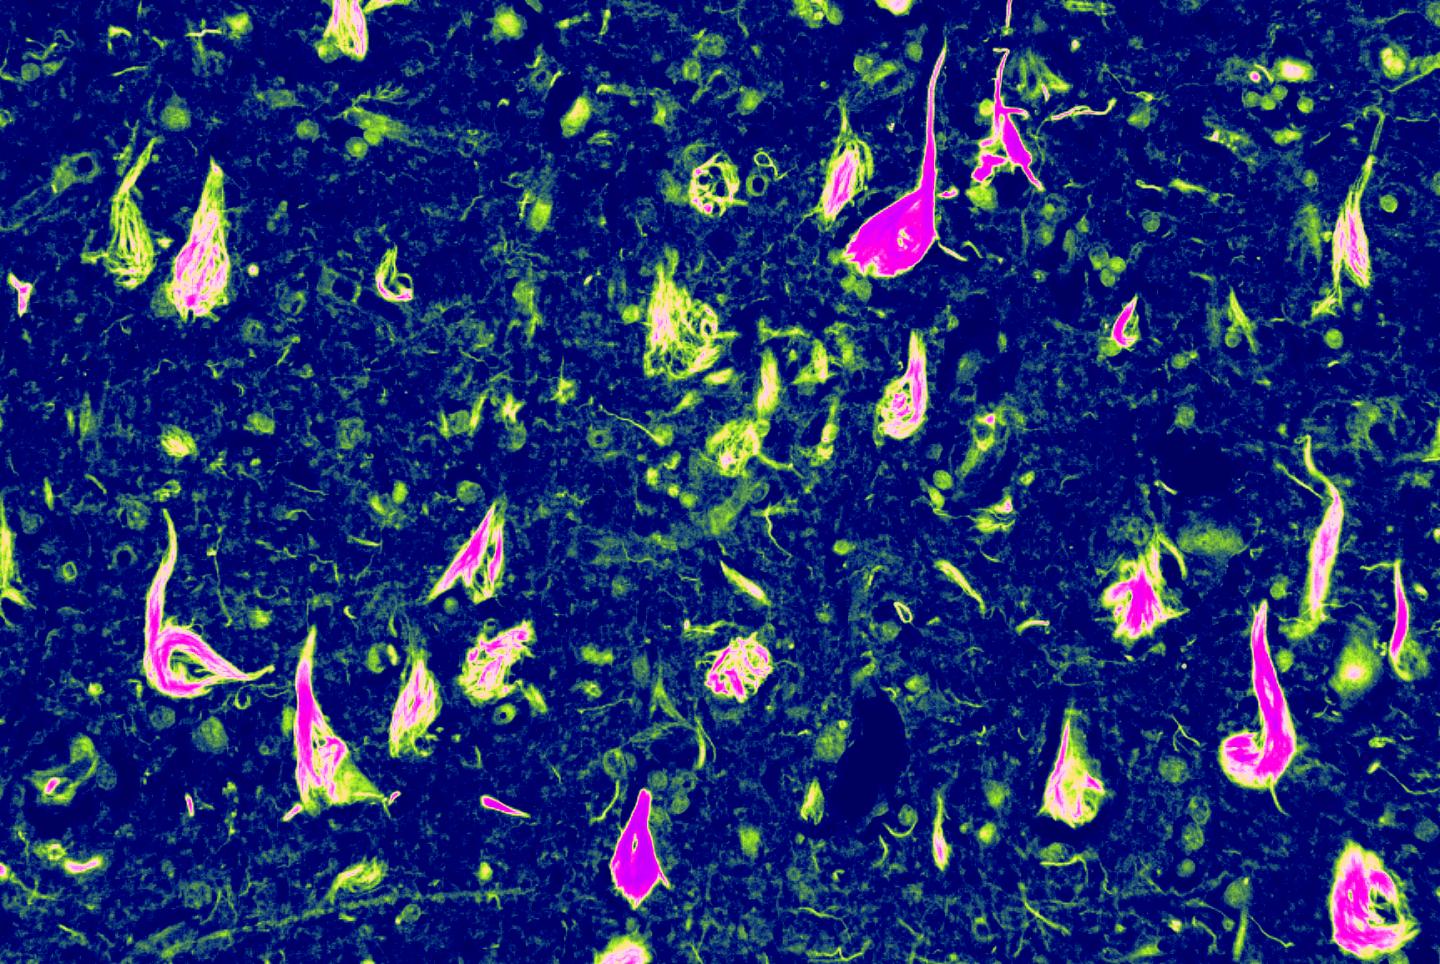

image: Abnormal neurofibrillary tangles (NFTs) -- a buildup of tau protein in parts of the brain -- helped Edward Lee, MD, PhD, an assistant professor of Pathology and Laboratory Medicine, and other Penn Medicine scientists uncover this new form of dementia.

Alzheimer's disease (AD) is a neurodegenerative disease characterized by a buildup of proteins, called tau proteins, in certain parts of the brain. Following an examination of human brain tissue samples from a deceased donor with an unknown neurodegenerative disease, researchers discovered a novel mutation in the Valosin-containing protein (VCP) gene in the brain, a buildup of tau proteins in areas that were degenerating, and neurons with empty holes in them, called vacuoles. The team named the newly discovered disease Vacuolar Tauopathy (VT)--a neurodegenerative disease now characterized by the accumulation of neuronal vacuoles and tau protein aggregates.